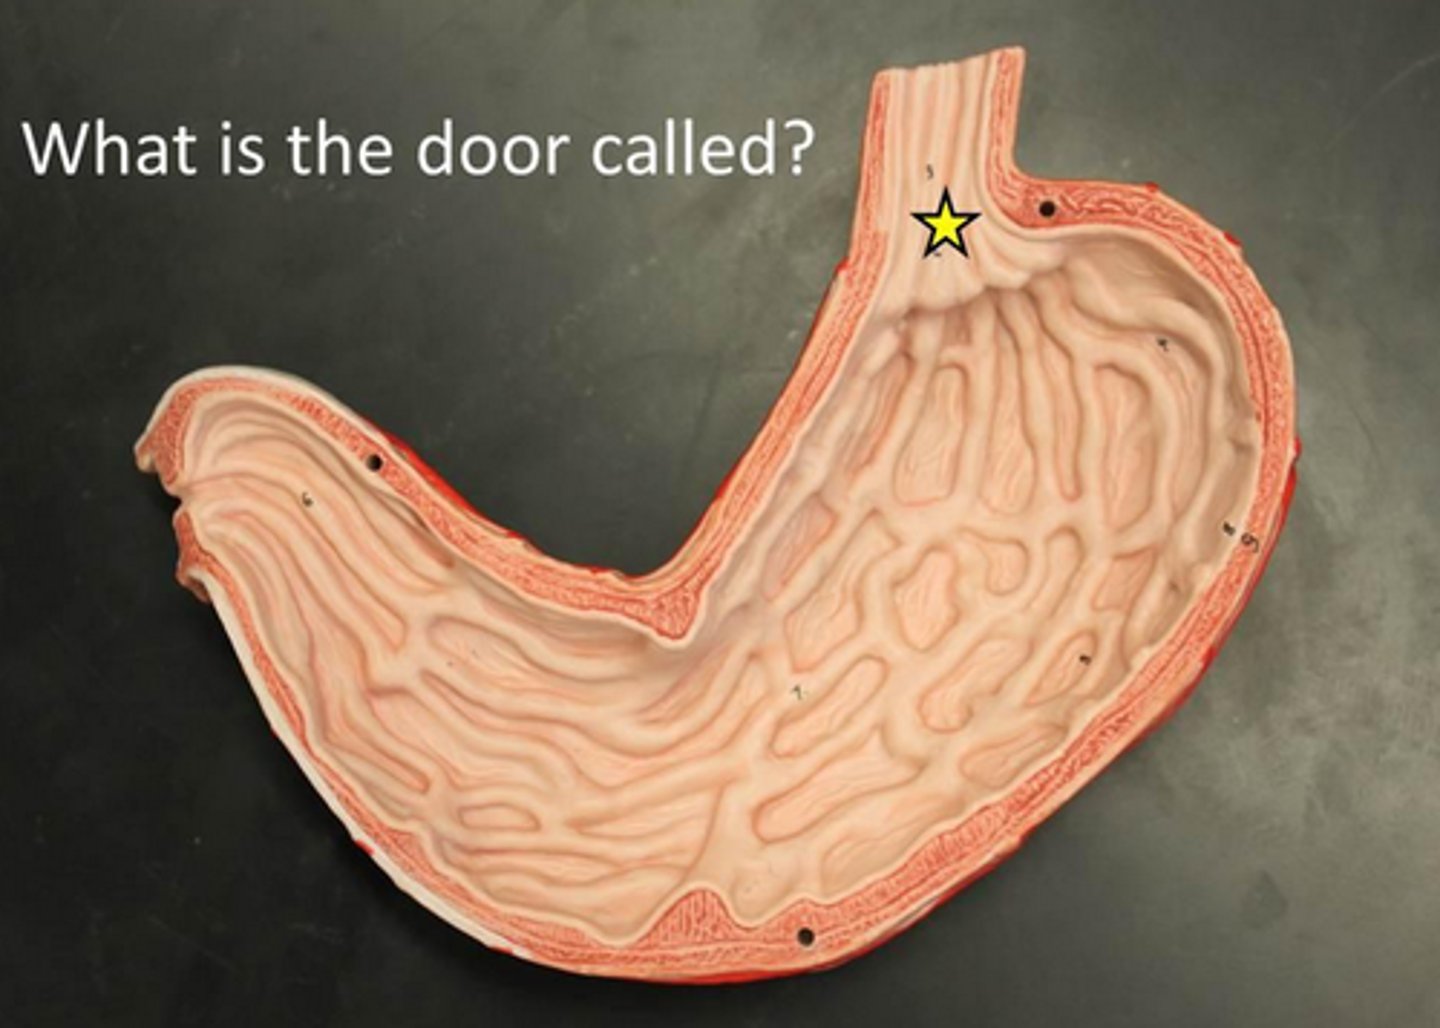

cardiac sphincter / lower esophageal sphincter